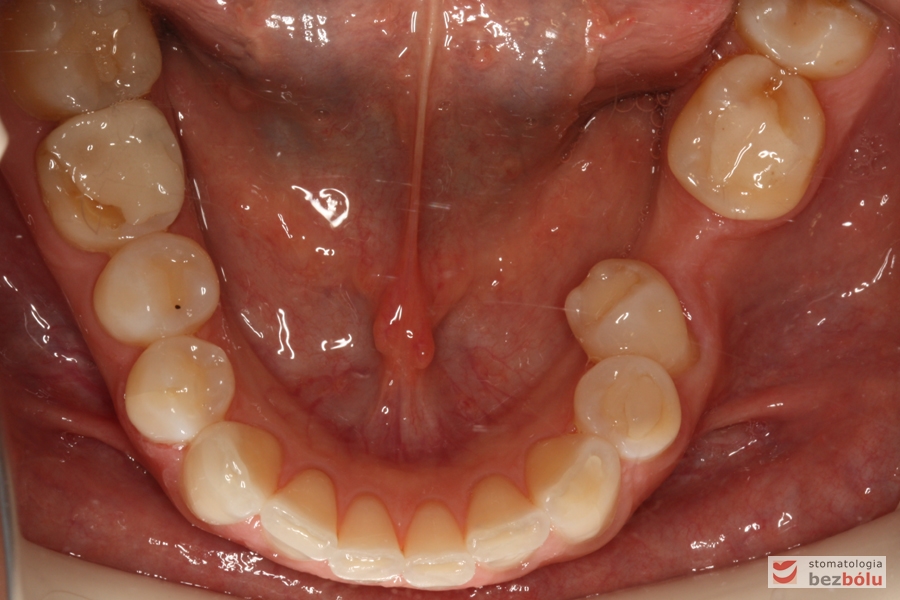

Żuchwa - widok okluzyjny - brak lewej szóstki, przechylona piątka

Żuchwa – widok okluzyjny – brak lewej szóstki, przechylona piątka